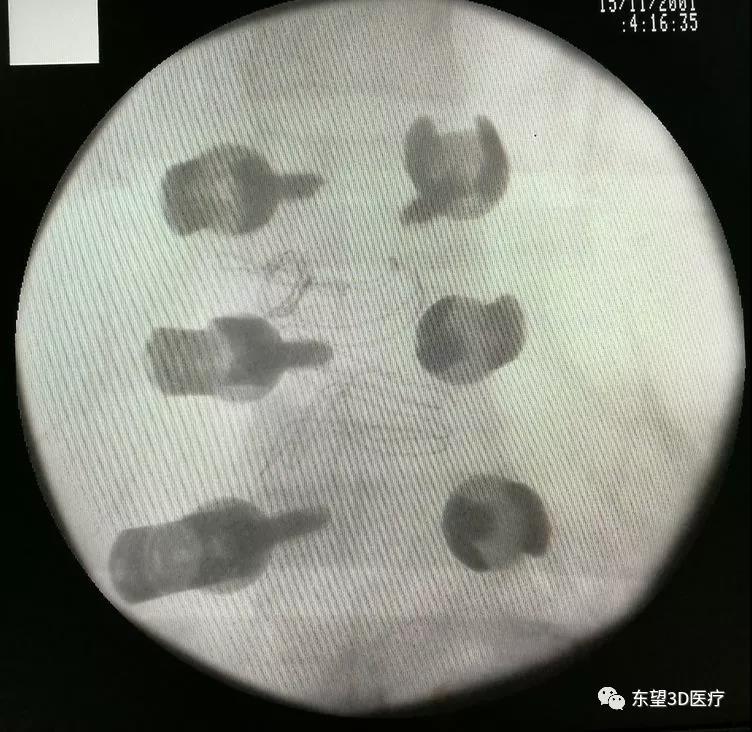

X線透視椎弓根釘位置準(zhǔn)確